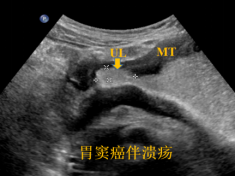

1、肿瘤性病变、炎性与溃疡性病变

2、对于胃占位性病变的大小、位置、尤其是胃壁的浸润程度进行全面评估